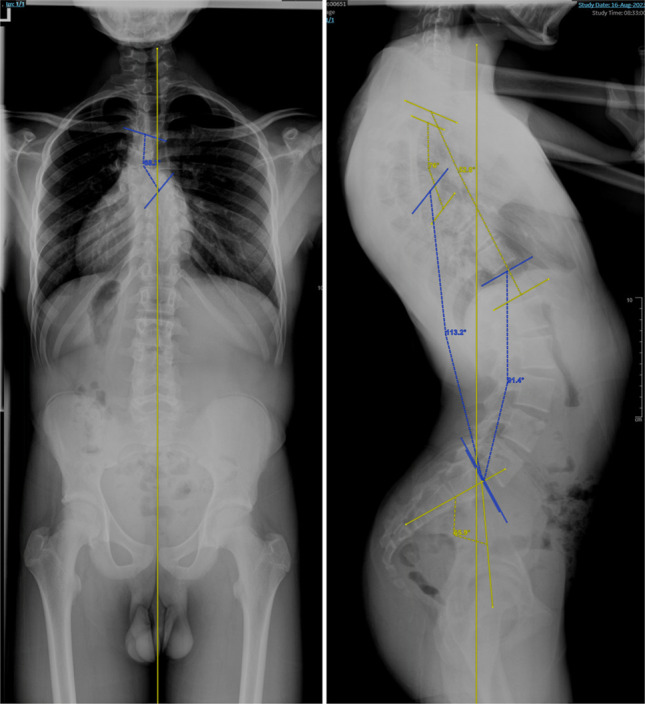

一个健康的15岁男性运动员表现为上胸椎先天性后凸,引起明显的疼痛和限制参加竞技体育。除了矢状面相关的中、下背部疼痛外,患者还对代偿性胸腰椎前凸的背部形状表示担忧,这与他期望的身体活动有关。影像学显示T4-T8与T6和T7的半椎体融合段异常。在保守治疗失败后,患者接受了T2-L2后路脊柱融合术和后柱截骨术,成功地恢复了矢状位,并允许恢复高强度运动。即使在稳定的、非进行性畸形中,也应考虑与异常矢状面脊柱对齐相关的不良症状。后路脊柱内固定融合矢状位矫正术可以有效地恢复先天性后凸脊柱侧凸伴胸腰椎前凸的矢状位和功能,改变畸形的自然历史,提高生活质量。

A healthy 15-year-old male athlete presented with upper thoracic congenital kyphoscoliosis, causing notable pain and limiting participation in competitive sports. In addition to mid and low back pain related to sagittal profile, the patient also expressed concerns regarding shape of his back from the compensatory thoracolumbar lordosis relative to his desired physical activities. Imaging demonstrated an abnormal fusion segment from T4-T8 with hemivertebrae at T6 and T7. After failing conservative management, the patient underwent T2-L2 posterior spinal fusion with posterior column osteotomies, successfully restoring sagittal alignment and allowing a return to high-impact sports. Unfavorable symptoms associated with abnormal sagittal spinal alignment should be considered even in a stable, nonprogressive deformity. Sagittal correction with posterior spinal instrumented fusion can effectively restore sagittal posture and function in athletes with congenital kyphoscoliosis associated with a sweeping and symptomatic thoracolumbar lordosis, altering the natural history of the deformity and improving quality of life.